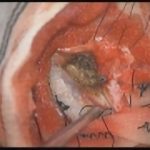

術中写真

摘出 前